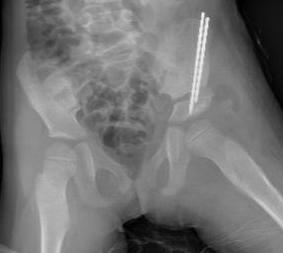

Osteotomy

- through greater sciatic notch to between ASIS and AIIS

- Gigli saw passed around greater sciatic notch

- osteotomy posterior to anterior

- acetabulum rotated anteriorly and laterally

- 15 mm triangular graft from iliac crest apophysis

- secure with K wire fixation

Salter complete osteotomy